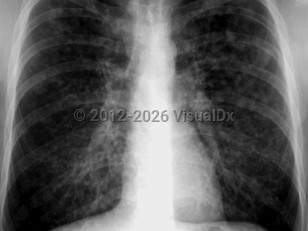

Chronic obstructive pulmonary diseaseChronic obstructive pulmonary disease

Pulmonary emphysemaPulmonary emphysema

Pulmonary edema